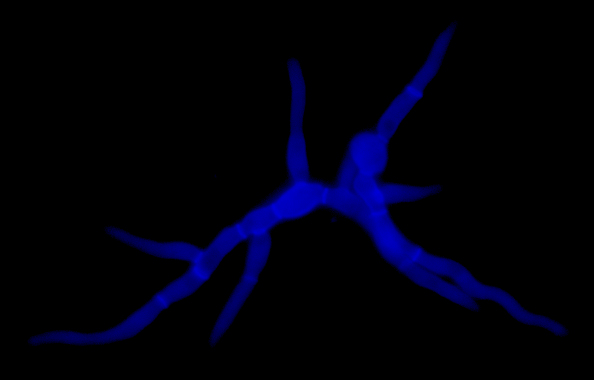

Crecimiento de Lomentospora prolificans. Tinción fluorescente del hongo (en azul; blanco de calcofluor) tras 8 horas de crecimiento a 37°C en medio líquido. -